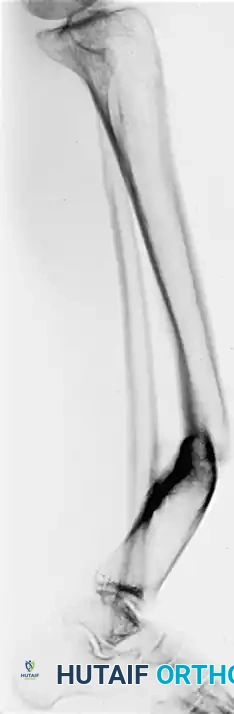

Image

1. Positioning and Exposure: The patient is positioned supine on a radiolucent table. A standard longitudinal incision is made over the anterior or anteromedial aspect of the tibia, taking care to preserve the periosteal blood supply.

2. Identifying the Plane: Under fluoroscopic guidance, the plane of maximal deformity is identified.

3. The Osteotomy: An oblique osteotomy is marked perpendicular to the plane of maximal deformity. Multiple drill holes are made along the planned osteotomy line to prevent thermal necrosis and control the propagation of the cut. The osteotomy is completed using a sharp osteotome or an oscillating saw under continuous saline irrigation.

4. Correction and Lengthening: The distal fragment is mobilized. Rotational and angular deformities are corrected manually. If lengthening is required, the distal fragment is translated distally along the oblique plane of the osteotomy.